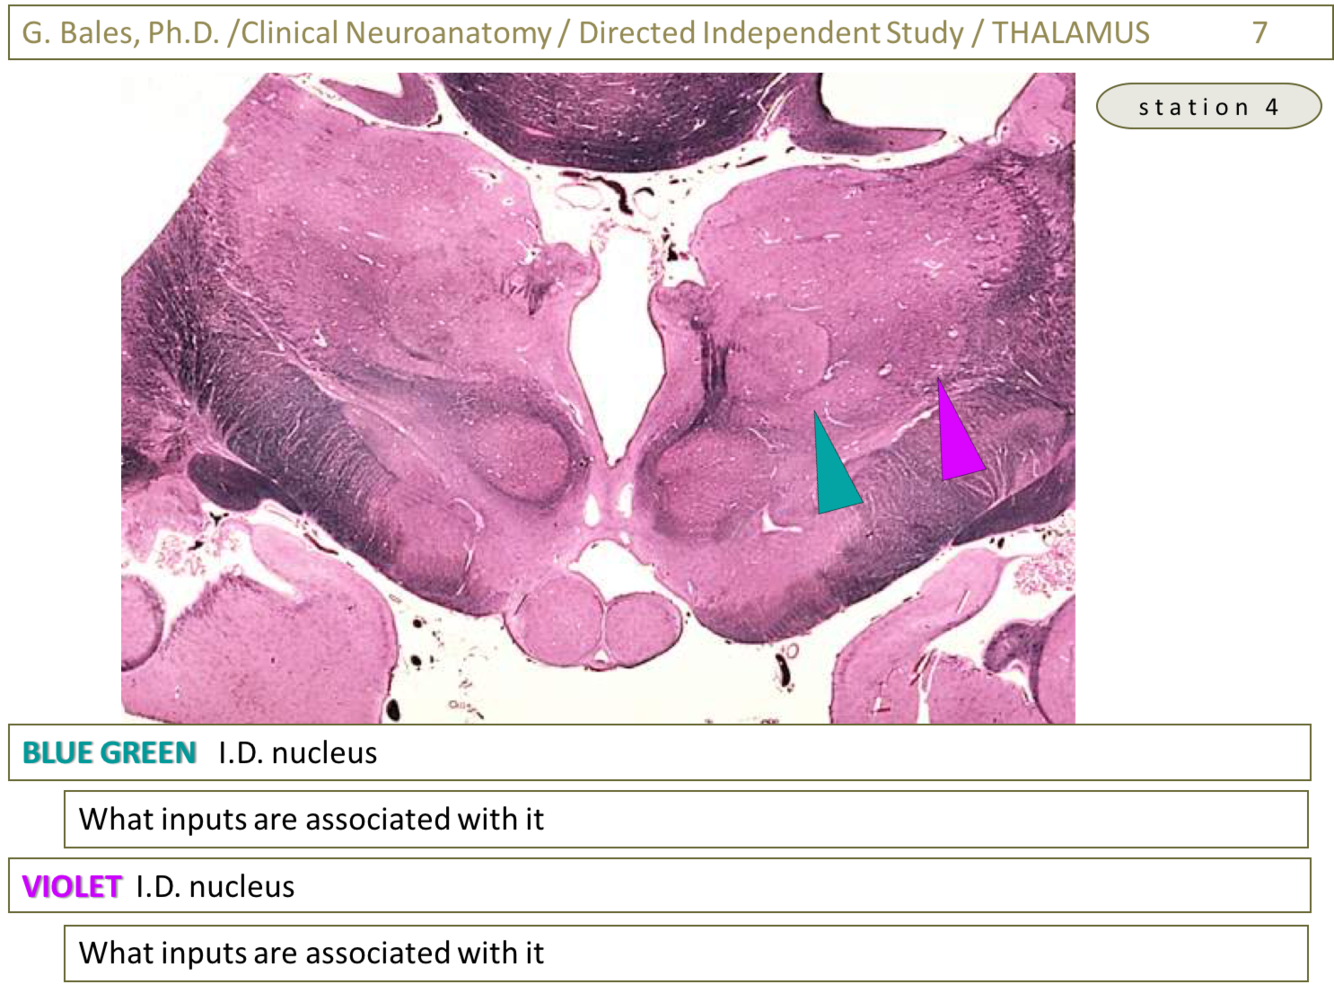

1) Ventral posterior medial nucleus (VPM) (Thalamus 2-Glass sections – slide 14)

1) Inputs from somatosensory cortex for face and anterior insula (taste) as well as the conscious trigeminothalamic and gustatory pathways (Thalamus lecture – slide 31)

2) Ventral posterior lateral nucleus (VPL) (Thalamus 2-Glass sections – slide 15)

1) Inputs from somatosensory cortex for limbs and trunk and also from the conscious somatosensory trunk and limbs (Thalamus lecture – slide 30)